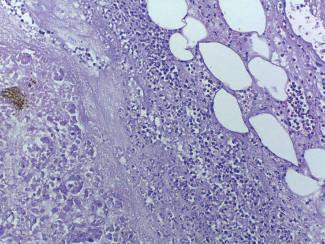

Identificação Genética de Desconhecidos

Palavras-chave: identificação humana; indivíduos não identificados; genética.

Keywords: human identification; unidentified individuals; genetics.

Introdução

A identificação de um indivíduo desconhecido, no âmbito médico-legal e forense, pode ser realizada por diversos mé todos científicos, de entre os quais destacamos a identifi cação genética, que, por regra, só é ordenada ou requerida quando nenhum dos outros métodos disponíveis possibili tou a identificação do indivíduo. Por este motivo e porque as situações que possam envolver um número de vítimas muito alargado são de reduzida ocorrência, em termos quantitativos, as perícias de identificação genética de des conhecidos não se encontram no topo das perícias mais realizadas no âmbito médico-legal e forense. Aliás, na his tória contemporânea de Portugal, o único desastre de mas sa que envolveu um número considerável de vítimas, que tiveram de ser identificadas recorrendo à identificação ge nética, ocorreu em 2017, ficando conhecido na história de Portugal como os incêndios de Pedrógão Grande. Não obs tante a casuística pouco expressiva em termos numéricos, nas primeiras décadas do corrente século XXI, o recurso às perícias de identificação genética tem-se generalizado a ní vel mundial em todas as situações de desastres de massa, chamando a si um papel de extrema importância quer em termos socias, quer em termos humanitários.

Neste capítulo abordamos o âmbito de aplicação da iden tificação genética, bem como os diferentes tipos de amos tras estudados no âmbito destas perícias, os marcadores genéticos utilizados, a valorização estatística dos resulta dos genéticos, as diferentes metodologias laboratoriais dis poníveis e, finalmente, alguns dos casos de identificação genética de especial relevância e interesse histórico.

A abordagem que fazemos à temática da identificação ge nética de desconhecidos tenta utilizar linguagem e nível de complexidade que permita a sua compreensão e, portanto, a sua utilidade, quer para académicos quer para profissio nais, quer sejam das áreas das ciências jurídicas e ciências sociais e humanas, quer sejam das áreas das ciências da vida e ciências médicas.

60.1

Identificação humana

Cada ser humano constitui-se com origem num suporte biológico que se sustenta com uma estrutura psíquica, ao qual as condições histórico-socioculturais em que se de senvolve vincam uma identidade. Este conjunto, que se traduz numa singularidade, numa realidade única, é assim reconhecido na relação entre indivíduos. A singularidade de cada ser humano é-lhe reconhecida pelos demais se res humanos e pela sociedade, não só durante todo o seu período de vida, mas também após a sua morte biológica. Neste alinhamento, o direito português confere a todo o ser humano, por força do princípio da dignidade da pessoa hu mana que inspirou a Constituição da República Portuguesa, o direito à identidade pessoal. Com o nascimento completo e com vida, todos os indivíduos adquirem simultaneamente a personalidade jurídica e inerentemente o direito à identi dade pessoal. Também a Declaração Universal dos Direitos Humanos, no seu artigo 6.º, estabelece que todos os indi víduos têm direito ao reconhecimento em todos os lugares da sua personalidade jurídica, e, portanto, da sua singulari dade e identidade pessoal.

Se é certo que a individualidade psíquica e sociocultural de um indivíduo pode ser moldável ao longo da sua vida, tal não se verifica, salvo situações absolutamente excecio nais, com a identidade genética que é, pois, o suporte da componente biológica de cada ser humano. À semelhança do conceito mais abrangente de identidade pessoal, a identidade genética assenta nas características de cada indiví duo, que se traduzam numa singularidade, numa realidade única e na possibilidade de reconhecimento dessa singula ridade entre diferentes indivíduos.

A identidade de um indivíduo presente aos serviços médico -legais, seja em vida seja em estado de cadáver, na grande maioria dos casos é verificada através daquilo que desig namos por identificação visual e que se baseia na compa ração de cada indivíduo que nos é presente com fotografias de documentos oficiais. No entanto, contrariamente ao que

© PACTOR 905

60

se passa com a maior parte dos indivíduos vivos ou cadá veres humanos frescos, a identificação visual não tem apli cação ou utilidade nos casos de cadáveres em avançado estado de decomposição, maioritariamente cadáveres es queletizados, em remanescentes humanos, em cadáveres recentes que apresentem mutilações, e em particular muti lações faciais, e, nem mesmo, em indivíduos vivos indocu mentados que não tenham, ou afirmem não ter, memória da sua identidade. Nestes casos, de acordo com orientações e consenso internacionais, a identificação individual mé dico-legal é realizada, sempre que possível, recorrendo à lofoscopia ou à informação médico-dentária. Ainda assim, quando nenhum destes métodos permitiu a identificação individual, a genética forense é então chamada a intervir para realização do exame pericial de identificação genética de desconhecido.

Sublinhar que, sendo os métodos de identificação indivi dual todos de natureza comparativa, a lofoscopia, relati vamente à identificação genética, tem, em princípio e na maior parte dos casos, a vantagem de ter quase sempre disponíveis dados para comparação em registos oficiais. É muito reduzido o número de situações em que um indiví duo não tem a sua impressão digital registada em arquivos oficiais. Já no que concerne a registos médico-dentários existem em número muito reduzido se comparados com os registos lofoscópicos oficiais.

Dada a necessidade de comparação, quanto menor e mais específico for o grupo que definimos e ao qual, em prin cípio, pertence o indivíduo ou remanescente humano a identificar, maior será a probabilidade de alcançarmos uma identificação individual positiva. Assim, o contributo prévio da intervenção pericial da antropologia forense, na orien tação da investigação da identidade, pode ser de grande valor. A intervenção pericial da antropologia forense desen volve-se no sentido de apurar o sexo biológico do indivíduo a quem pertencem os remanescentes humanos em estudo, bem como de estimar a sua idade aproximada à altura da morte, a sua estatura e robustez, ancestralidade ou afinida des populacionais, o tempo decorrido post mortem e, even tualmente, algumas informações de especial relevância na individualização dos remanescentes humanos bem como algumas informações no âmbito das causas e circunstân cias da morte. Com o conjunto de informação reunida em resultado da atividade pericial da antropologia forense, o grupo de indivíduos onde se poderá incluir o cadáver ou os remanescentes cadavéricos a identificar será tão reduzido quanto possível, possibilitando, desta forma, maior suces so das intervenções periciais subsequentes, sejam elas da medicina dentária forense sejam elas da genética forense (Amorim, Afonso-Costa, et al., 2011).

A identificação genética de desconhecidos, como já des crito anteriormente, por norma, só é ponderada quando nenhum dos restantes métodos científicos de identificação

médico-legal humana permitiu identificar o cadáver ou os remanescentes cadavéricos. Para este alinhamento con correm essencialmente dois fatores. Por um lado, o facto da identificação genética ser dos métodos periciais mais complexos e mais laboriosos e, por outro lado, o facto da identificação genética ser dos exames periciais mais dis pendiosos em termos de recursos financeiros. Mais ainda, e nesse aspeto não trazendo qualquer diferença ou vanta gem relativamente aos restantes métodos de identificação médico-legal humana, a realização das perícias de identifi cação genética de desconhecidos só é possível se existir um referencial para comparação, seja este uma amostra de referência do suposto indivíduo a identificar colhida an tes da sua morte, sejam objetos pessoais utilizados antes da morte pelo suposto indivíduo a identificar, sejam estes ascendentes diretos, descendentes diretos ou familiares com outros graus de parentesco biológico relativamente ao suposto indivíduo a identificar que concordam de forma livre e informada em ceder amostras biológicas suas para utilização no âmbito da identificação genética de um ca dáver desconhecido a identificar, sendo, aliás, esta última situação o referencial mais frequentemente utilizado, se não mesmo o único possível, no âmbito das perícias de identifi cação genética de desconhecidos realizadas pelos serviços médico-legais.

De há mais de 20 anos a esta parte, a identificação gené tica de desconhecidos, sob responsabilidade dos serviços médico-legais e forenses, concretiza-se através da deter minação do perfil genético do cadáver ou remanescentes cadavéricos a identificar, perfil este que se constitui como o conjunto de informação em determinado número, grupo ou painel de marcadores genéticos, observada no genoma do indivíduo ou remanescentes a identificar.

Existem recomendações científicas internacionais no âm bito das perícias de identificação genética de desconheci dos, relativas a várias matérias, das quais destacaríamos as recomendações relativas às qualificações mínimas dos peritos que realizam as perícias e as recomendações rela tivas aos marcadores genéticos a utilizar na realização de perícias de identificação genética de desconhecidos.

Quanto às qualificações mínimas dos peritos responsáveis por perícias de identificação genética, de acordo com a au toridade internacional competente para a área, a International Society for Forensic Genetics (ISFG), as perícias de identificação genética, aliás como quaisquer outras perícias inseridas no âmbito da genética forense, deverão ser rea lizadas por indivíduos com formação universitária de du ração mínima entre cinco a seis anos, na área da genética humana ou outra área adequada ou afim, e experiência tu telada mínima de três anos, em laboratório e com supervi sor que, também estes, cumpram estas recomendações da ISFG (Morling et al., 2002).

Tratado

Legal 906

de Medicina

Quanto aos marcadores genéticos a utilizar, as recomenda ções internacionais e designadamente as recomendações da autoridade internacional com competência na matéria –European DNA Profiling Group (EDNAP) –, determinam que os marcadores genéticos a utilizar na definição de perfis genéticos no âmbito da identificação humana são os de signados STR (do inglês short tandem repeats), também conhecidos como microssatélites ou como ADN não codi ficante repetitivo em tandem. O elenco dos STR em utiliza ção em cada país, quer em termos quantitativos quer em termos qualitativos, é determinado com base em critérios técnicos e científicos rigorosos e bem definidos que, por seu lado, permitem sempre alguma flexibilidade na decisão final das autoridades políticas competentes, e designada mente no que se refere ao número de STR a utilizar.

60.2

Âmbito de aplicação

A identificação genética de desconhecidos no âmbito mé dico-legal, em regra e como já referido anteriormente, tem sempre lugar quando nenhum outro método científico de identificação humana permite identificar um indivíduo ou re manescentes humanos, podendo, no entanto, por decisão de autoridade judicial ou judiciária ou por decisão do perito médico titular do processo, ser o único método utilizado em determinadas situações em concreto, ainda que, esta segunda alternativa seja de ocorrência excecional.

A identificação genética pode ter por objeto um único indi víduo ou remanescentes humanos com origem num único indivíduo, ou remanescentes humanos com origem em múl tiplos indivíduos. O indivíduo, remanescentes humanos ou

indivíduos a identificar podem ser indivíduos vivos ou ca dáveres, sendo, no caso destes últimos, as situações mais comuns as dos cadáveres esqueletizados (Figura 60.1). Genericamente, no que se refere aos cadáveres presentes para identificação genética de desconhecidos, as situações mais frequentes na rotina pericial dos serviços médico-le gais resultam quer de mortes naturais por doença ou por outros fatores intrínsecos ao indivíduo, quer de mortes vio lentas, nas quais incluímos os suicídios, os homicídios e os acidentes, sejam estes, acidentes rodoviários, incêndios, explosões, derrocadas, naufrágios ou outros.

Quando estamos perante acidentes ou quaisquer fenó menos cuja magnitude e, sobretudo, o número de vítimas, impliquem a necessidade de assistência externa, segundo a Organização Mundial de Saúde (OMS), estamos perante situações que se classificam como desastres de massa. Os principais desastres de massa ocorridos na história da hu manidade têm resultado da ocorrência quer de catástrofes naturais, como erupções vulcânicas, tsunamis, furacões, ciclones, terramotos, inundações, secas extremas, incên dios, de entre outras, quer de acidentes de aviação, quer, ainda, de conflitos bélicos ou de outros conflitos políticos e atos terroristas, dos quais, em regra, o número de vítimas é muito elevado e o número de vítimas a submeter a perícias de identificação genética de desconhecidos pode, também, ser muito elevado.

Para além de indivíduos vivos ou cadáveres para identifica ção genética de desconhecidos no âmbito das situações até aqui elencadas, os serviços médico-legais recebem, ainda, para identificação genética, remanescentes de inter rupções de gravidez (Figura 60.2), fetos ou remanescentes fetais (Figura 60.3), recém-nascidos, bem como amostras biológicas que classificamos como amostras dúbias.

Identificação Genética de Desconhecidos 907 © PACTOR

Fig. 60.1 Corpo esqueletizado, para identificação Fig. 60.2 Remanescentes de interrupção da gravidez, para identificação do pai biológico

Quanto à identificação genética de desconhecidos que tenha lugar em amostras provenientes de remanescentes fetais ou embrionários, sublinharíamos que o artigo 42.º do Código Penal Português prevê que, após interrupção da gravidez ordenada na sequência de crime sexual de viola ção, deve ocorrer identificação genética dos remanescen tes embrionários ou fetais por comparação com a amostra do presumível agressor/pai biológico. Já no caso de na dos-vivos ou mortos em que tenha ocorrido o abandono, a identificação genética tem lugar com vista ao apuramento de quem terá sido a presumível responsável pelo abando no/mãe biológica.

Quanto ao que habitualmente designamos como amostras dúbias, podem ser amostras colhidas no âmbito da realiza ção de análises clínicas ou de outros exames complemen tares de diagnóstico, como exames anátomo-patológicos, e, designadamente, sangue ou fragmentos de tecidos hu manos dos mais diversos órgãos e localizações, e relativa mente às quais não há a certeza do indivíduo, da pessoa a quem pertencem, a quem se referem. As amostras dú bias podem, ainda, ser amostras colhidas não no âmbito do diagnóstico médico, mas no âmbito de exames periciais de toxicologia forense, designadamente sangue colhido em contexto de determinação de alcoolémia ou de determi nação de drogas de abuso, bem como amostras colhidas no âmbito de controlos de dopagem em atletas. Comum a todas as amostras dúbias elencadas é o facto de não exis tir, ou de ter sido levantada suspeição sobre, a verdadei ra identidade do indivíduo a quem pertence determinada amostra e, portanto, a quem ficará associado, a quem será atribuído, determinado diagnóstico médico ou a prática da utilização ilegal de determinada substância ou substâncias.